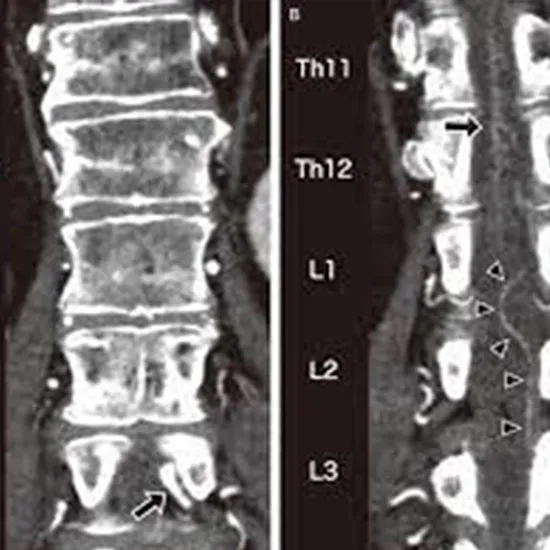

Contrast Enhanced Computerized Tomography Dorsal Spine is abbreviated as CECT DORSAL SPINE. It is an imaging procedure used to obtain cross-sectional images of the vertebral column's lumbar region. The scan aids in the creation of 3-D images of the spinal column, vertebral bones, intervertebral discs, and soft tissues surrounding the spine.

CT of the spine is a diagnostic imaging test used to help diagnose or rule out spinal column damage in injured patients. CT scanning is quick, painless, non-invasive, and precise. It can reveal internal injuries and bleeding quickly enough in an emergency situation to help save lives.